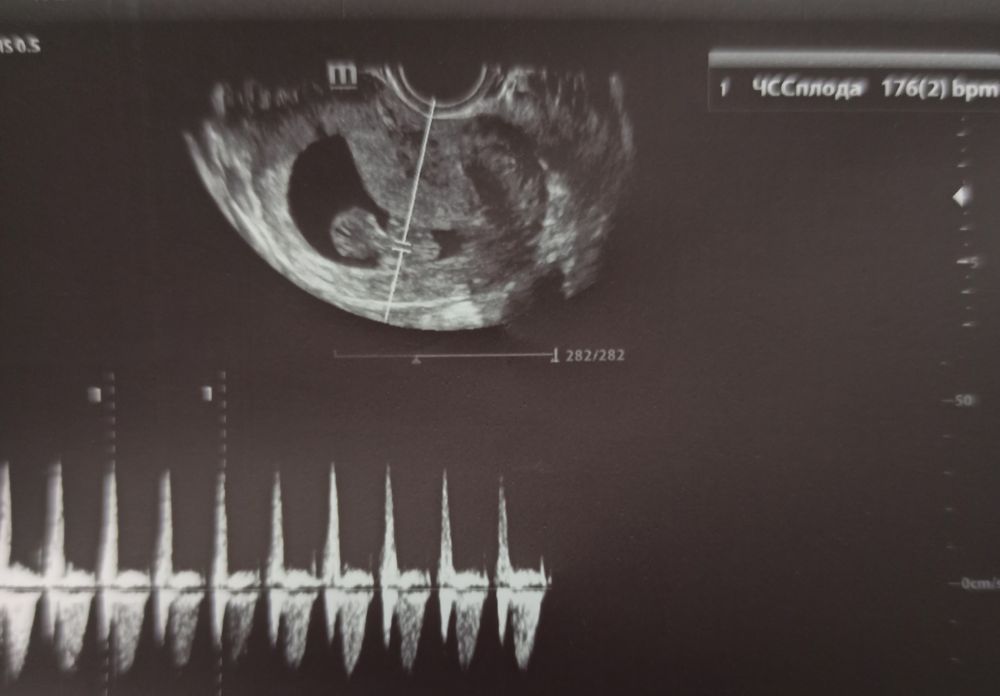

Сегодня 12 апреля на 57 дпо ( 10 недель и 1 день) на УЗИ: ПЯ 59 мм, КТР 38 мм, ЧСС 174 уд/мин, ЖМ 5,5 мм, киста ЖТ 25*23 мм, опережаем на 4 дня, видела как шевелил ручками и ножками человечик, и также врач показала с разных ракурсов мальчишеский писюлëк, мне даже кокошки показались, но для них наверно ещё рано, пока мне не верится, неужели это и правда СЫН 👶 дракончик 🦕 скорпиончик 🦂 Слушаю домашним допплером сердечко с 9+4❤ , пишет 170-180 уд/мин, совпадает с данными УЗИ. На самом нижнем фото врач показал слева это ножки и стопы две вместе, а справа это попа и писюлька( вид снизу), я сама бы не поняла что это.